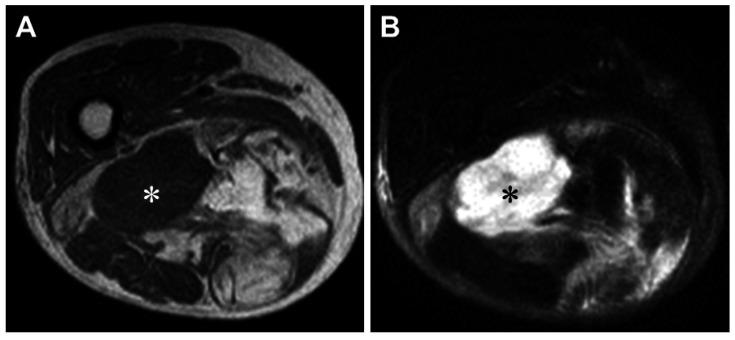

去分化脂肪肉瘤(DDL)被定义为从高分化脂肪肉瘤(WDL)/非典型脂肪瘤性肿瘤(ALT)向非脂肪生成性肉瘤的转变,其主要发生于腹膜后和近端肢体的深部软组织。它的特征是有额外的环状和巨大标记染色体,两者均包含12q13 - 15的扩增序列,包括()和()细胞周期致癌基因。检测(和/或)扩增有助于将DDL与其他未分化肉瘤区分开来。最近,在一部分DDL中发现了 - 融合基因。然而,与WDL/ALT去分化相关的遗传事件仍有待阐明。局限性DDL的标准治疗方法是手术,可联合或不联合放疗。对于晚期疾病,标准的一线治疗方案是以蒽环类药物为基础的方案,可使用单药蒽环类药物,或蒽环类药物与烷化剂异环磷酰胺联合使用。不幸的是,该方案不一定能带来令人满意的临床结果。对DDL发病机制认识的最新进展可能有助于开发更有效的创新治疗策略。本综述概述了目前关于DDL的临床表现、发病机制、组织病理学和治疗的知识。